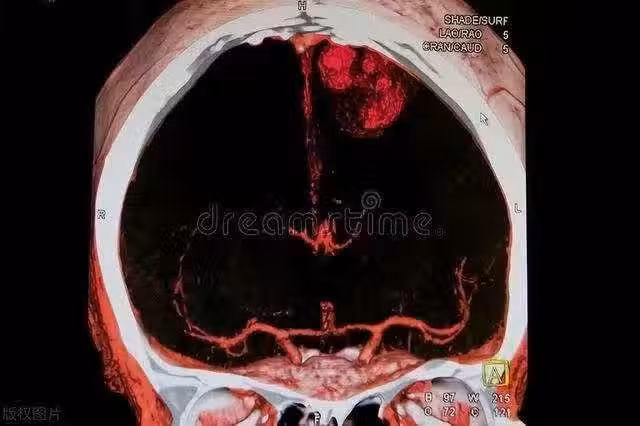

提醒:身體的3個異常,是腦中風發出的「紅色警告」,忽視不得!

識別並及時響應中風的徵兆可能會挽救一個人的生命或避免長期的殘疾。

無論您是否有中風的風險因素,都應該對這些「紅色警告」保持警惕。身體給出的信號不應被忽視。

如有任何疑慮或出現上述症狀,請立即尋求醫療幫助。您的及時行動可能會使自己或他人得以生存。